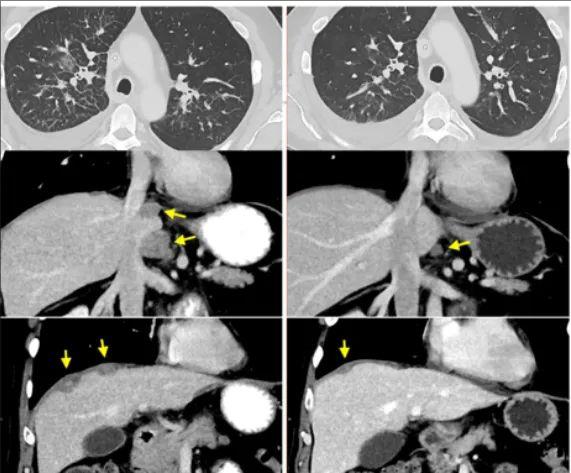

患者二、转移性结肠癌患者,支气管镜记录的右肺淋巴管炎受累(顶部,轴向)、腹膜后淋巴结和肝周肿瘤(中和底部,冠状方向)的消退

患者三、转移性直肠癌患者的肝转移、门管淋巴结和多个肺转移的消退